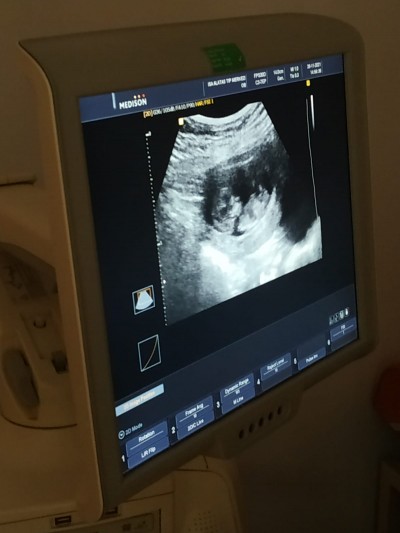

Cinsiyetine çok merak ediyorum:)))

12+1 cinsiyetini görebilen varsa yazarsa sev

12+1

Erkeğe benziyor

Erkek gibi duruyor ama zaten olsa doktor benzetir kıza göre erkekler çabuk beli oluyor

İçimden erkek geçti nedense